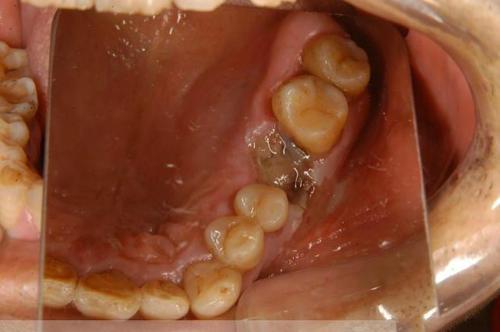

2) Les symptômes cliniques du stade intermédiaire peuvent inclure des saignements des gencives, la destruction de l'infiltration osseuse et des dents déchaussées et douloureuses. À ce stade, les symptômes ont tendance à être plus marqués, il est nécessaire de procéder à des examens d'imagerie dentaire tels que des radiographies, si nécessaire, ainsi qu'à des examens pathologiques afin de clarifier le diagnostic.

Toute personne présentant des masses gingivales inexpliquées, des érosions ou des maux de dents avec des dents déchaussées, une fenêtre qui ne guérit pas pendant une longue période après l'extraction d'une dent ou des ulcères en forme de cratère sur les gencives, en particulier ceux qui ont plus de40Les personnes âgées de plus de 18 ans doivent se rendre à l'hôpital pour des contrôles réguliers. En règle générale, elles ne doivent pas utiliser leurs doigts ou une brosse à dents pour enlever les bosses naissantes sur leurs gencives, afin de ne pas provoquer d'infections.Aggravation.

Le cancer gingival précoce, en particulier lorsqu'il est confiné à la marge gingivale ou aux papilles interdentaires, est facilement diagnostiqué à tort comme une gingivite ou une parodontite ; deuxièmement, les lésions ulcéreuses précoces, en particulier les marges gingivales diffuses accompagnées de douleurs, peuvent également être diagnostiquées à tort comme une tuberculose gingivale. Le diagnostic clinique des maladies susmentionnées doit être attentif à la possibilité d'un carcinome gingival, et l'examen radiographique montre une destruction osseuse en forme d'éventail de l'os de la mâchoire, avec des bords ressemblant à des vers.

Les symptômes du cancer des gencives se manifestent principalement par l'apparition d'un gonflement sur les gencives ; avec le temps, le gonflement augmentera progressivement en taille, changera de couleur, se fissurera, se brisera, saignera, etc. Avec la progression de la tumeur, dans les cas graves, des dents déchaussées et des mâchoires cassées apparaîneront également, et si la tumeur a des métastases dans les ganglions lymphatiques, elle se manifestera également par l'élargissement du cou.